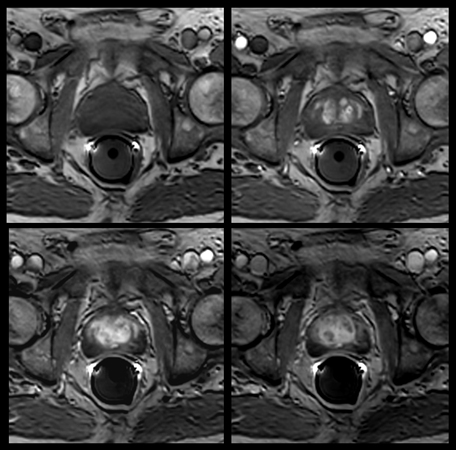

Prostate imaging with dS Endo + dS Torso coil

• Clinical Application